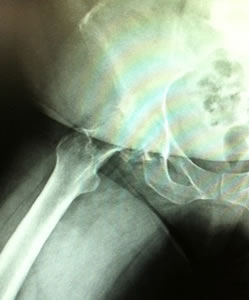

Dr. Testerman's cas is a forty-five year old female, morbidly obese with bilateral hip disease. She is currently household ambulatory and otherwise confined to a wheel chair, although able to independently transfer herself to and from bed. X-rays show destructive bilateral OA of the hip with such severity it is hard to determine if the underlying disease is hip dysplasia or not. The right hip head has collapsed making true measurement of femoral offset difficult.

Due to her relative young age, body weight and the likely fact that she will be facing one or more revisions in her lifetime Dr. Testerman decided a more bone conservative tissue sparing approach would be in her best interest. Although her body weight certainly did not lend itself to a conservative soft tissue approach this device does not require resection into the greater trochanteric and abductor musculature area.

At 5' 2" and 250 lbs this was going to be a challenge for any approach, devise, and surgeon. In addition this was being done at a new hospital with a new team that had not seen this devise before. Prior to surgery, John and I had a chance to review the x-rays and we did not see anything that should hinder the selection of the ARCTM Stem. We did have a conventional stem on backup and always recommend that a conventional stem be available. I did suggest that he take an intraoperative x-ray once the trials were implanted.

| X-ray confirmed our impression that we could go up in size of the stem and neck length. The offset appeared to be good with a neutral modular neck and 0 head with a 36 mm poly insert. |